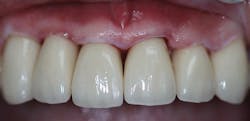

A final impression was made using a base VPS impression material (V-Posil Putty Fast, Voco; figure 11) followed by a light-body VPS impression material wash (V-Posil Light Fast, Voco; figure 12). A provisional crown was made using a cold-cure composite provisional material (Structur 3, Voco; figures 13 and 14) andcemented. The patient was dismissed. Upon return three weeks later, the provisional was removed and the definitive laboratory-fabricated zirconia crown was delivered.

Figure 14: Provisional crown